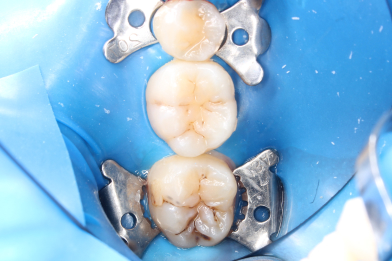

Д.12 лет. Жалобы на реакцию, на сладкое и холодное между зубами 16,15.

Колиш Максим Петрович

При осмотре обнаружен контактный кариес на зубах 16,15.

Лечение в один визит, восстановление функциональности композитной реставрацией. -